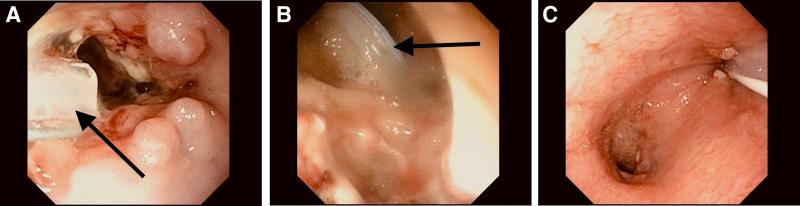

Surgical repair of type C esophageal atresia (EA) with distal tracheoesophageal fistula (TEF) is complicated by an anastomotic leak in 10%-30% of cases with associated morbidity. A novel procedure in the pediatric population, endoscopic vacuum-assisted closure (EVAC), accelerates the healing of esophageal leaks by using the effects of VAC therapy, including fluid removal and stimulation of granulation tissue formation. We report 2 additional cases of chronic esophageal leak treated with EVAC in EA patients. The first is a patient with a previously repaired type C EA/TEF and left congenital diaphragmatic hernia complicated by an infected diaphragmatic hernia patch erosion into the esophagus and colon. Additionally, we discuss a second case using EVAC for early anastomotic leak following type C EA/TEF repair in a patient who was later found to have a distal congenital esophageal stricture.

C型食管闭锁(EA)合并远端气管食管瘘(TEF)的手术修复在10%-30%的病例中会出现吻合口漏,并伴有相关并发症。在儿科人群中,一种新的手术方法——内镜下真空辅助闭合术(EVAC),通过利用负压封闭引流(VAC)疗法的作用,包括液体清除和刺激肉芽组织形成,加速食管漏的愈合。我们报告另外2例EA患者采用EVAC治疗慢性食管漏的病例。第一例患者曾接受C型EA/TEF修复手术,合并左侧先天性膈疝,并发感染性膈疝补片侵蚀食管和结肠。此外,我们还讨论了第二例病例,一名患者在C型EA/TEF修复术后早期出现吻合口漏,采用EVAC治疗,该患者后来被发现患有远端先天性食管狭窄。